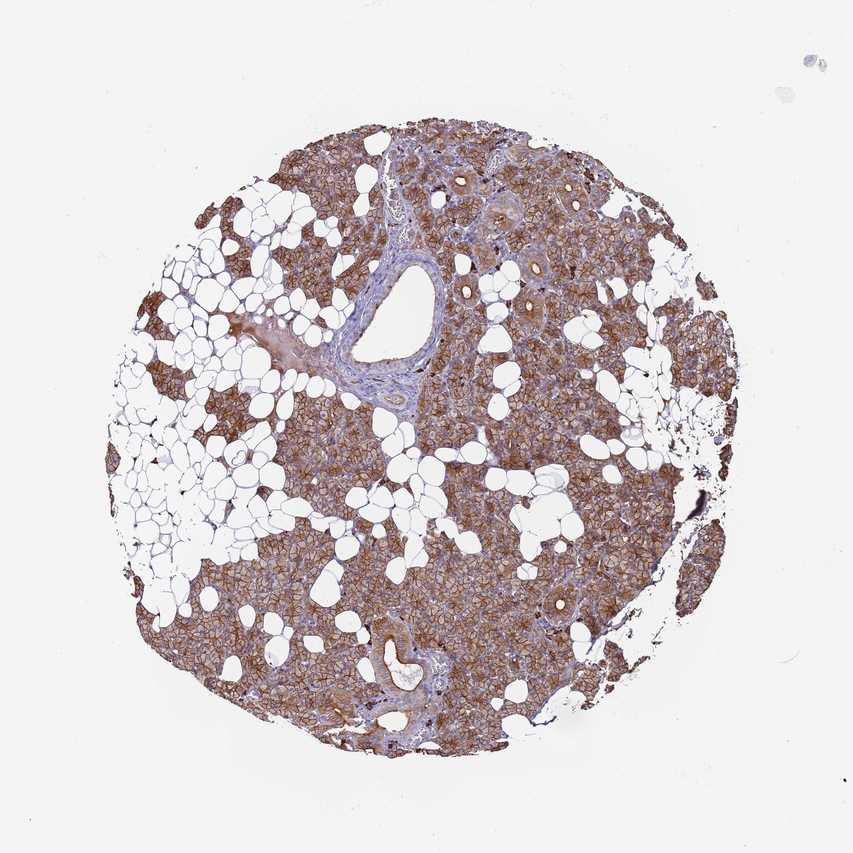

SALIVARY GLAND - Antibody stainingi

Antibody staining in the annotated cell types in the current human tissue is reported as not detected, low, medium, or high, based on conventional immunohistochemistry profiling in selected tissues. This score is based on the combination of the staining intensity and fraction of stained cells.

Each image is clickable and will lead to virtual microscopy that enables deeper exploration of all samples and also displays staining intensity scores, fraction scores and subcellular localization as well as patient and tissue information for each sample.

Antibody HPA046528

Glandular cells High